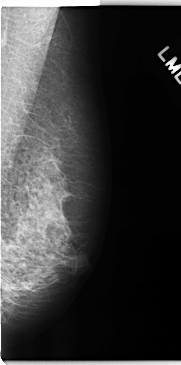

C_0193_1.LEFT_MLO

LEFT_MLO LINES 4736 PIXELS_PER_LINE 2352 BITS_PER_PIXEL 12 RESOLUTION 50 NON_OVERLAY